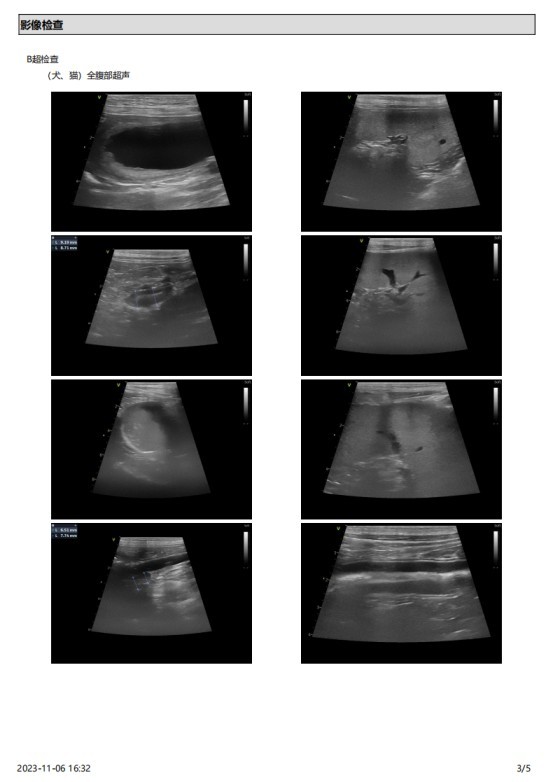

主诉最近发现两只睾丸的大小相差较大,精神状态尚可,挑食。于近日入院进行病变部位的超声检查,结果如图:

该图为肿大的左侧睾丸

2023 年 10 月份检查结果